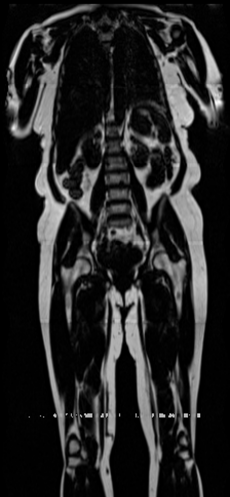

Our results unequivocally highlight the superior performance of X-Diffusion in terms of both qualitative and quantitative metrics. Representative MRI volumes generated by our pipeline, when juxtaposed with ground-truth images, showcased remarkable similarity, with even intricate physiological features like tumor information, spine curvature, and fat distribution being accurately captured.

Notably, X-Diffusion achieves sota dB for a few input slices while baselines require more than 60 input slices to achieve similar performance (Figure 7). The margin is more than 12 dB PSNR for the 1-slice input in both the BRATS and the UK Biobank benchmarks (see Table 1 and Figure 6). For reference, two randomly sampled MRIs from the UK Biobank would have a PSNR of 15.95 dB 0.36 (on 4800 randomly sampled examples). The slices from 3D reconstructed volumes at varying depths and axis of rotation visually match the ground truths (see Figures 5 and Figure 4). We also plot the error map (Figure 4) of such X-Diffusion generations to highlight the differences with the ground truth MRIs.

Preservation of Spine Curvature. For the spine segmentation on UK Biobank, we use a UNet++ model [81] with Dice Loss and use the curvature prediction of the spine followed in [9]). We measure the Pearson correlation factor [9] of spine curvature measured on the generated MRIs where the input is a single MRI coronal slice, or a single sagittal slice against the curvature of reference real MRIs of the same samples. The correlation coefficients are 0.89 for the coronal MRIs and 0.88 for the sagittal MRIs on the test set of 308 human-annotated angles.

UK Biobank. A more comprehensive dataset of 48,384 full-body MRIs from more than 500,000 volunteers[67]. UK Biobank MRIs are resampled to be isotropic and cropped to a consistent resolution (501 160 224). 48,384 whole-body MRIs are paired with antero-posterior (AP) DXA scans of the same subjects. These Dixon MRIs do not come stitched, the scans are scanned axially and there is a disparity in the bias field effect (a common artifact of MRI machines) which is strongest at the knee region. These Dixon MRI patches could not be stitched seamlessly with our current pipeline. These artifacts appear on all scans of the UKBiobank that we stitch. Therefore, the X-Diffusion trained on this data will recreate these artifacts regardless of input. The same pattern is present on all samples in the dataset for a fixed depth, while different depth indices will have different fixed patterns. We made sure there was a coherence split, such that each patient was in a unique set. We will publish the unique IDs used for train-validation-testing to confirm there is no leakage, nor retrieval of images. Both datasets are pre-processed to ensure compatibility with the X-Diffusion pipeline and to maximize the fidelity of the generated results. Pre-processing includes data normalization to the range [0,1], conversion to fit the RGB channel expected from the pre-trained diffusion model via replicating the grayscale to each channel, and padding to fit network input resolution 256x256x3.

B.3 Preservation of Spine Curvature and Fat

For the spine segmentation on UK Biobank, we use a UNet++ model [81] with Dice Loss. We use a model trained to predict curves on DXA on UK Biobank [9]. We show in Figure 20 that generated MRIs preserve the spine curvature from normal to severe scoliosis cases. We also study the case when DXA is used to generate the MRIs and show in Figure 14 how the correlation to real curvatures compares to the input MRI case. The curvatures of the MRI generated from the coronal plane match the DXA curvatures more than the curvatures generated from sagittal MRI. This is expected since the antero-posterior plane of DXA is equivalent to the coronal plane for MRIs. This also explains the greater Pearson’s correlation coefficient of the coronal MRI (0.89) and DXA-generated curvature (0.88) compared to sagittal-generated curvature (0.87) relative to the reference curvature on the coronal plane. We observe though that MRI generation using X-Diffusion from another plane than the conventional plane for scoliosis assessment is valid.